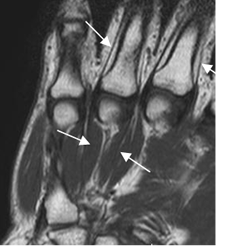

Los ligamentos también son bien estudiados con la RM. El grupo de intrínsecos es mejor visualizados en secuencias coronales y los extrínsecos en cortes sagitales. (4). Se identifican como estructuras delgadas, con baja señal de intensidad (SI) en todas las secuencia, adyacente a estructuras óseas y rodeados por grasa. (Fig 24 a 27).

Fig 24. Ligamentos intrínsecos normales.

A: RM coronal en T1, B: RM coronal en STIR y C: RM coronal en GE.

Ligamento escafolunado (Flecha delgada) y ligamento semilunopiramidal (Flecha gruesa).